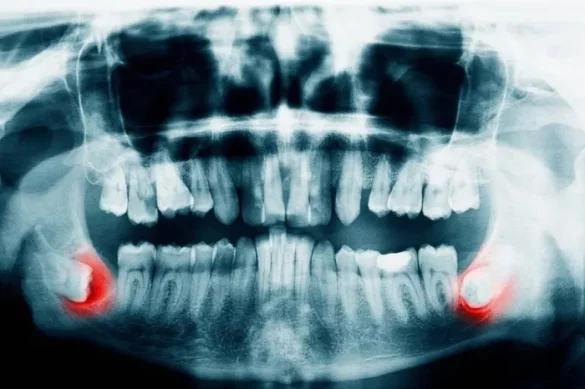

Wisdom teeth removal is a type of oral surgery where one or more of your third molars, known as wisdom teeth, are extracted. These teeth are located at the back of the mouth and are often removed because they can cause problems with crowding, alignment, or infection. Dentists or oral surgeons usually perform the procedure in an office setting under local or general anesthesia.

- Whether the teeth are impacted (trapped beneath gum or bone)